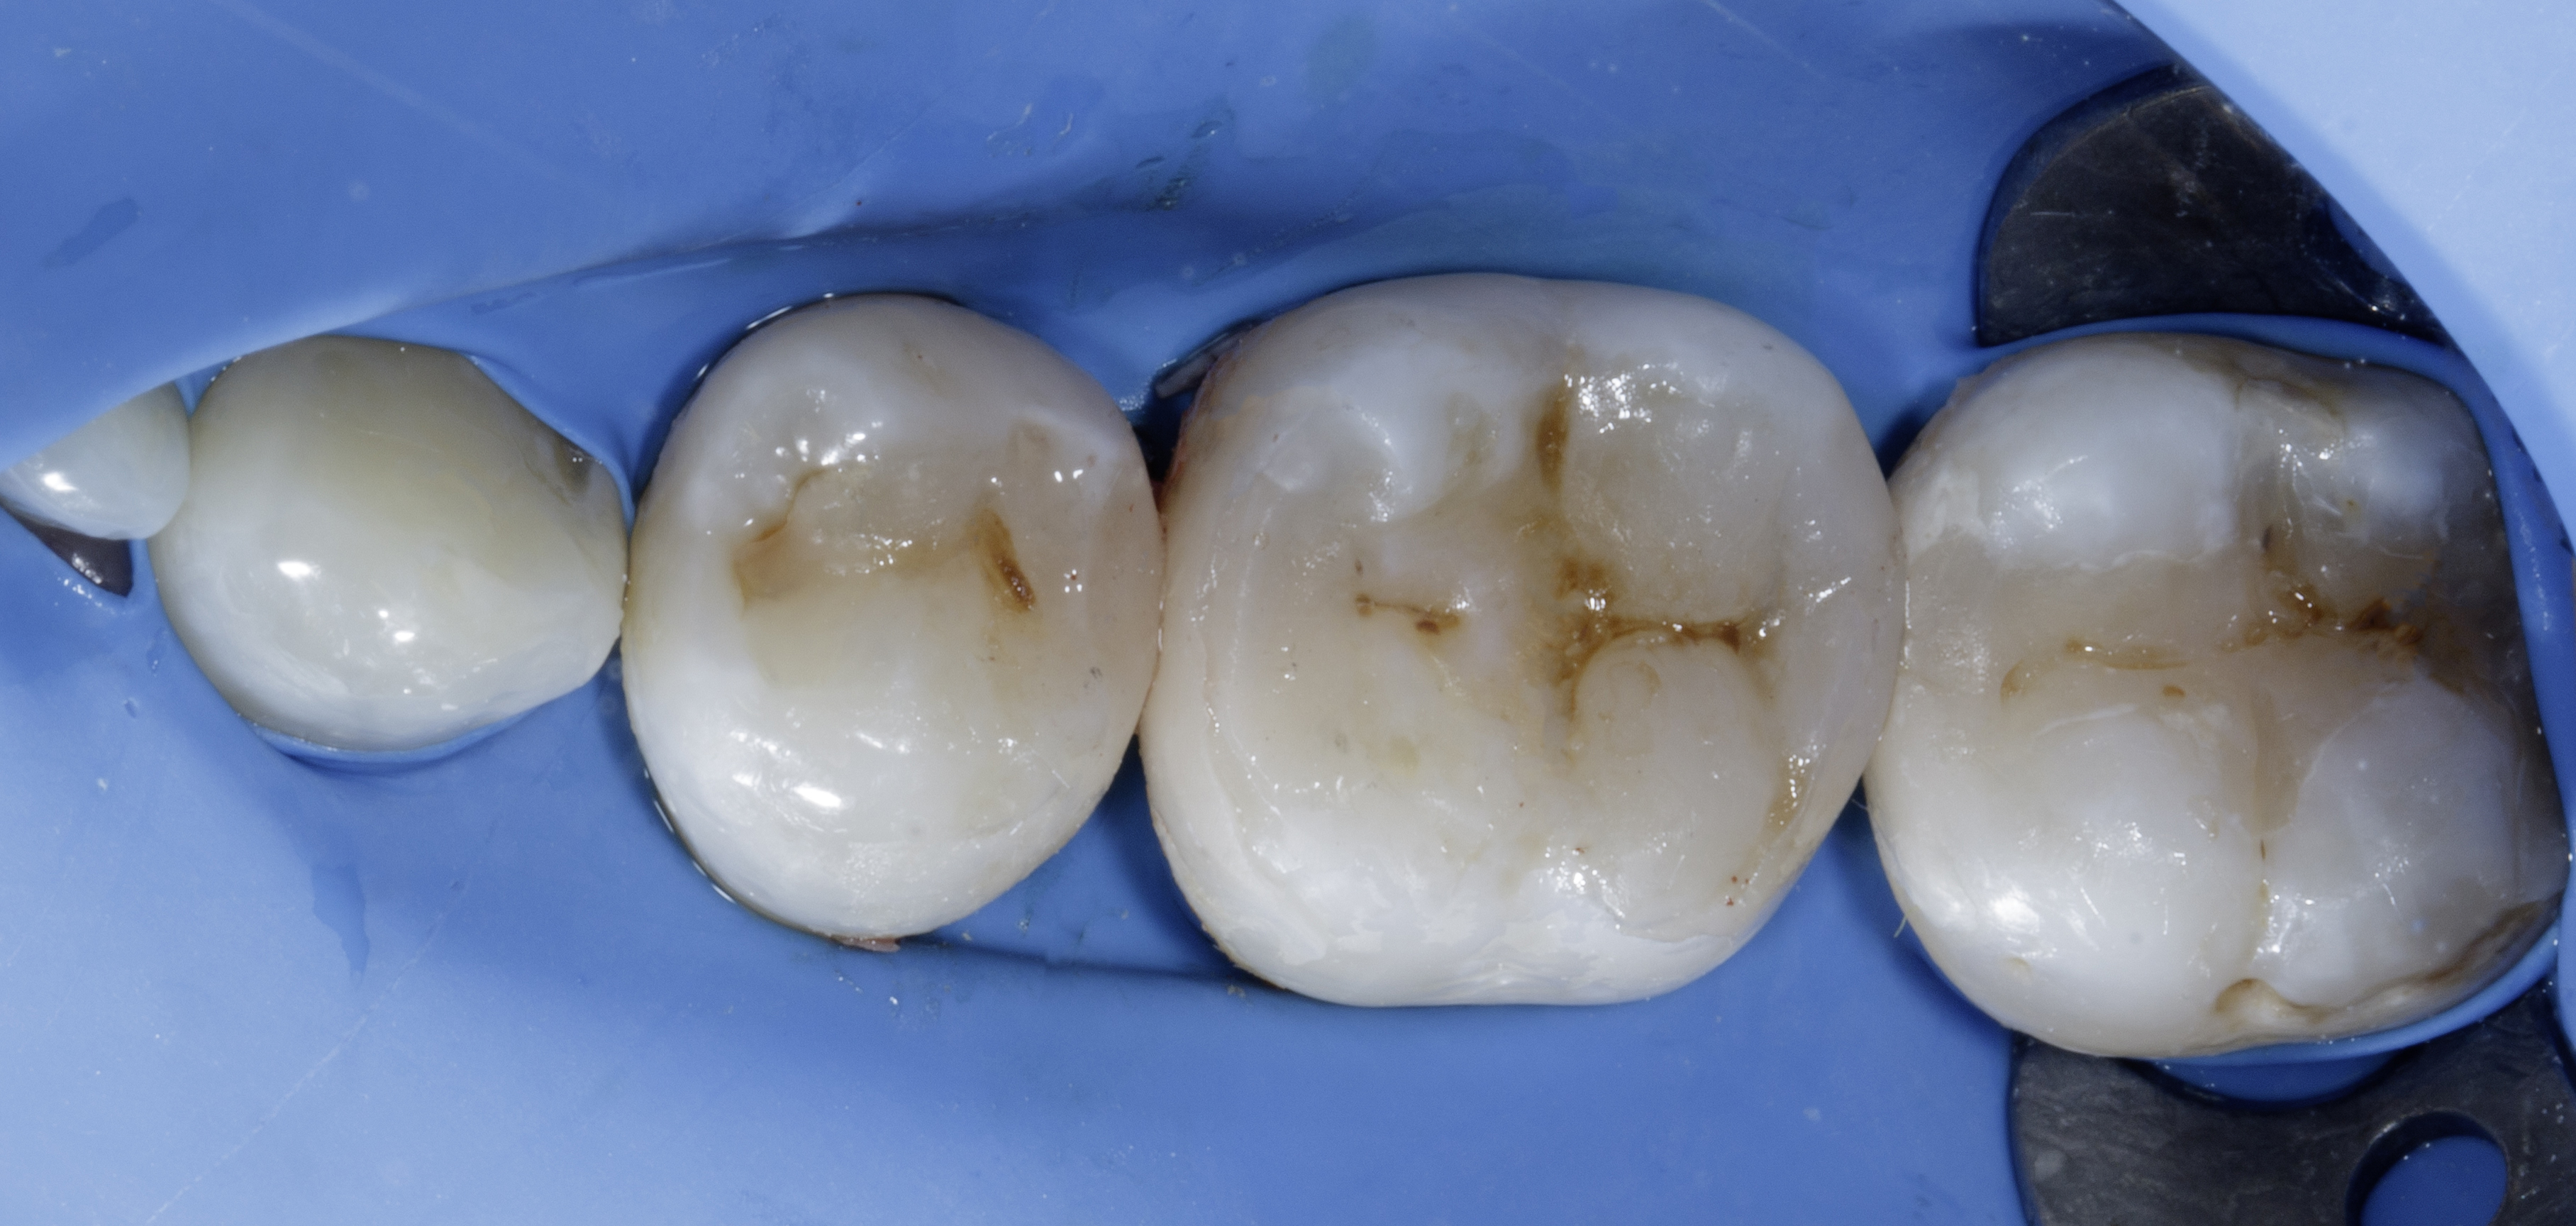

Figure 3

Figure 3.

The collage displays the prepared teeth after caries removal, addressed as follows:

- #48: Mesial tunnel preparation with an occlusal Class 1 defect.

- #47: Mesio-occluso-distal (MOD) defect preparation.

- #46: Class 2 defect preparation involving removal of unsupported enamel on the distobuccal cusp.

All preparations focused on removing caries, establishing a peripheral seal zone, eliminating unsupported enamel, and refining the proximal box.